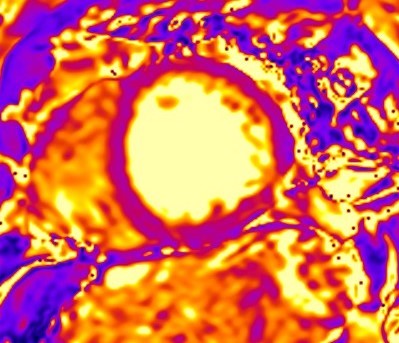

To overcome these limitations, T2 mapping, a parametric image of each voxel, was developed. T2 mapping values are independent of body size and/or heart rate and have good reproducibility [11]; however, they may vary between different scanner types or field strengths and for this reason the definition of individualized normal values for each center is strongly recommended [19, 20]. Increased signal on T2 mapping is an index of myocardial oedema, due to any kind of recent myocardial injury [11] (Fig. 4).

Fig. 4.CMR oedema evaluation using parametric imaging. T2

mapping in patient with polymyositis and ventricular arrhythmias (T2 mapping = 62

msec, normal values